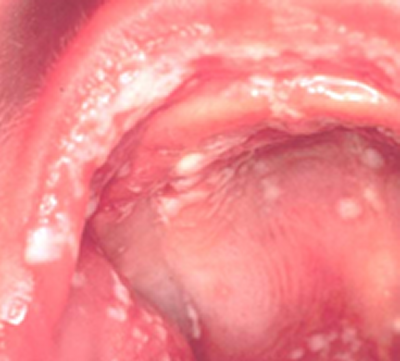

Inhaleeritavad kortikosteroidid suurendavad Candida (Candida albicans - suu seeninfektsiooni põhjustav pärmiseen) hulka suuõõnes, mis kliiniliselt väljendub atroofilise või pseudomembranoosse vormina.

Haigetel, keda ravitakse kortikosteroididega on glükoosi sisaldus süljes ja igemetasku vedelikus märkimisväärselt kõrgem. See võib samuti soodustada Candida kasvu, prolifereerumist ja kinnitumist.

Kortikosteroidide põhjustatud vormid on tavaliselt atroofiline (äge / krooniline) ja pseudomembranoossne. Ilmuvad valged või hallid katud, mis on kergesti ära kraabitavad ja alt veritsevad. Suu limaskest on valulik. Ägeda atroofilise kandidoosi korral pseudomembraanid on irdunud ja limaskestadel on ühtlane või laiguline punetus (erütematoos).

Üks haiguse vorm on kipitav keel (glossodynia).

Kroonilise atroofilise kandidoosi puhul on suu limaskestal difuusnne punetus ja üksikud ebakorrapärased punetavad laigud (Tyldesley 1989.)

Tavaliselt on haige kaebusteks:

- suuõõne limaskesta valu

- põletustunne

- veritsemine või “karvane” tunne suus

- maitsetunde muutumine.